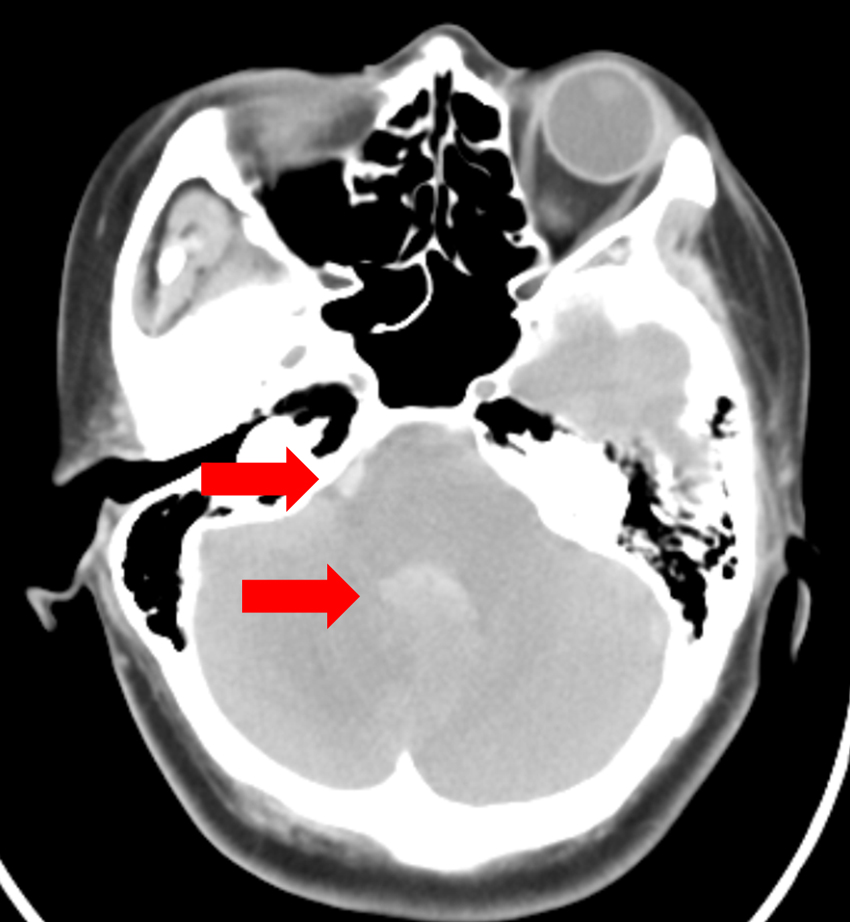

除夕夜,一名49歲女性突發劇烈頭痛、嘔吐,晚間意識不清送醫,檢查發現大量蜘蛛膜下腔出血及腦室內出血,確診為顱內動脈瘤破裂。急診立即插管,並由神經外科完成動脈瘤夾閉手術,大年初二剛好是患者生日,術後逐漸恢復清醒,四肢活動正常。

腦動脈瘤破裂引起的出血(箭頭處)。腦動脈瘤破裂引起的出血(箭頭處)。